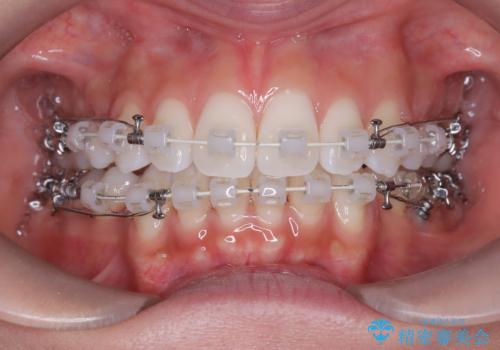

- 患者さんは「口元を引っ込めたい」「八重歯をきれいにしたい」とのご希望で来院されました。診察の結果、上下の前歯が前方に傾斜し、口元がやや突出して見える状態でした。加えて、上顎には八重歯があり、歯列のスペース不足も確認されました。

歯並びと横顔のバランスを整えるためには、前歯を後方に移動させるスペースの確保が必要です。そのため、上下左右の第一小臼歯(合計4本)を抜歯し、ワイヤー矯正で前歯の突出感と叢生(がたつき)を同時に改善する治療計画を立てました。歯を抜くことに抵抗がある方も多いですが、口元の印象を変えるためには非常に効果的な方法です。

上下左右の小臼歯を抜歯後、ワイヤー矯正装置を装着し、全体のバランスを見ながら歯を移動させていきました。特に前歯の後方移動では、抜歯スペースを活かして口元を内側に下げることに重点を置きました。また、八重歯も時間をかけて丁寧に整列させ、左右の正中(真ん中の位置)もぴったりと揃えることができました。